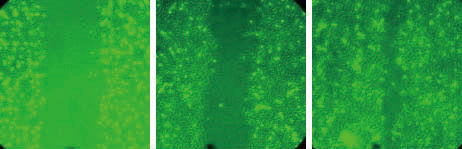

在证明微粒化之SACCHACHITIN对兔子角膜SIRC细胞株具有良好的增生效果後,另外又再进行一组实验,观察SACCHACHITIN是否会对SIRC细胞株之移行(Migration)也有帮助。方法就是先让SIRC细胞株在培养皿中长满,用一定大小之刮勺去除中间的细胞,再加入250μg/ml微粒化之SACCHACHITIN,并於24小时後观察刮除之部分有无细胞移行进来,结果如[图3]。

【图3】左图为细胞进行刮除後所留下没有细胞之中间部位 (0小时);

中图为对照组,不添加任何物质,只更换培养基(24小时後);

右图为实验组,除更换培养基外,

也添加250 μg/ml微粒化之SACCHACHITIN(24小时後)。